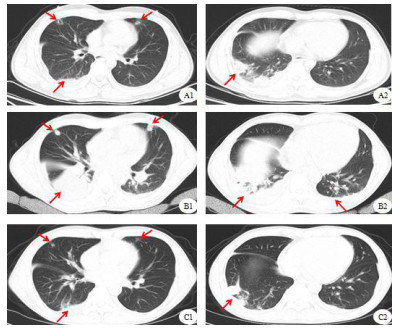

| A图:右侧前臂T2WI;B图:左侧前臂T2WI肌间隙多发长条高信号,结合DWI高信号、ADC值减低,考虑脓肿;病变如箭头所示 图 2 患者肌肉核磁图像 |

2021年1月4日转入急诊内科,追问病史,患者入院前2周右侧阴囊区疼痛,未诊疗,查超声:右侧附睾尾可探及一1.9 cm×1.4 cm大小混合回声,考虑炎症改变,继续青霉素+利奈唑胺抗感染。至1月6日仍持续低热,查体发现患者双侧上臂、前臂、双侧大腿、左侧小腿多发质硬条索状包块,皮温高。肌肉核磁示双侧上臂、前臂肌群肿胀渗出,考虑感染性病变并脓肿形成(图 2),复查胸部CT较前加重(图 1B1、B2)。行超声引导下肌肉脓肿穿刺、胸腔穿刺引流,穿刺液培养结果均阴性。现阶段肾功能恢复,将抗生素更换为青霉素240万单位q4 h+万古霉素1 g q12 h。1月13日患者再次出现高热,体温39.2 ℃,抽取血培养阴性,复查白细胞27.96×109/L,中性粒细胞比率0.90,降钙素原7.60 ng/mL,1, 3-β-D葡聚糖检测、半乳糖甘露醇聚糖抗原检测阴性,万古霉素血药浓度15.8 μg/mL,多学科讨论后给予达托霉素0.5 g q12 h抗感染治疗,因达托霉素不用于肺炎的治疗,故联用利奈唑胺600 mg q12 h,后患者症状逐渐缓解,再无发热,感染指标逐渐降至正常,肌力恢复,复查胸部CT好转(图 1C1、C2),于1月27日顺利出院。出院前为系统评估病情,行正电子发射计算机断层扫描检查:双肩及左肩胛旁、右髂翼至股骨小转子旁软组织肿胀并条片状低密度影,双侧髂内肌、臀部、大腿上段皮下软组织代谢增高,以上均考虑炎性病变,右臀部至大腿上端脓肿形成;双肺多发小结节/条片及絮状影,代谢不等增高,结合过往CT结果考虑炎性病变;右侧附睾局部代谢不均匀增高,多考虑炎性摄取。出院诊断:肺脓肿、脓胸、肌肉多发脓肿、肾周感染、附睾脓肿、感染性多脏器功能障碍综合征、感染性休克、急性呼吸衰竭、急性肾损伤、急性肝损伤、横纹肌溶解。出院后口服利奈唑胺1个月,3月2日、4月15日分别于本科复查,四肢脓肿、肺脓肿吸收,附睾脓肿较前缩小。